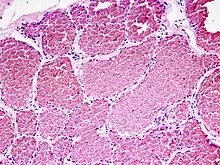

Formen:

- Kapilläres Hämangiom

- Kavernöses Hämangiom

| .jpg.webp) Kapilläres Hämangiom der Haut, Hautbiopsie, H&E. | .jpg.webp) idem, stärkere Vergrößerung  | .jpg.webp) Kavernöses Hämangiom der Leber, Resektat, H&E. |